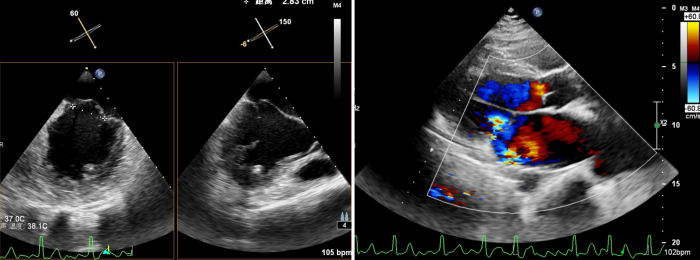

术前心脏彩超所示:二尖瓣返流

术前,超声科聂红军教授运用全数字化高端心脏彩色多普勒诊断仪,为患者进行食道三维超声综合评估,确定了二尖瓣返流量及返流分区。同时,在手术中实时监测二尖瓣瓣叶返流区与钳夹器的位置是否吻合,术后还可即刻探查二尖瓣返流量减少情况,如果把手术比作开车,那超声科就是手术的导航系统。

术中,蒋路平主任团队在经食道超声引导下通过股静脉穿刺房间隔将二尖瓣钳夹系统送入患者左心房到达二尖瓣口,然后医生全程在经食道超声引导下通过评估二尖瓣返流位置以及返流程度等精准夹合二尖瓣叶,整个过程都是在心脏不停跳的情况下完成。